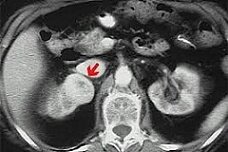

Как сообщает 1rre.ru, в ходе социологического опроса стало известно, что женщины зачастую не знают самых общих симптомов рака яичников.Эта болезнь занимает четвертое место в списке смертельно опасных женских недугов. Врачи уверяют, что плохая осведомленность женщин является одной из причин высокой смертности от рака яичников.

Самыми общими симптомами данного заболевания являются частые вздутия и боли в области живота. По данным статистического комитета Великобритании ежегодно диагноз рак яичников ставится более чем семи тысячам женщин. Ввиду плохой осведомленности пациенток диагноз ставится на поздних стадиях, когда болезнь уже не остановить.

Сегодня нас окружает множество рисков и сложностей. Рак - это всегда испытание не только для того, кто заболел, но и для всех, кто его окружает. Очень важно осознавать, что жизнь на этом не заканчивается и есть возможность победить болезнь, но для этого нужно правильно и вовремя ее диагностировать. Самый распространенный вид рака у женщина - это рак яичников(http://ztema.ru/illness/onkologiya/rak-yaichnikov/).